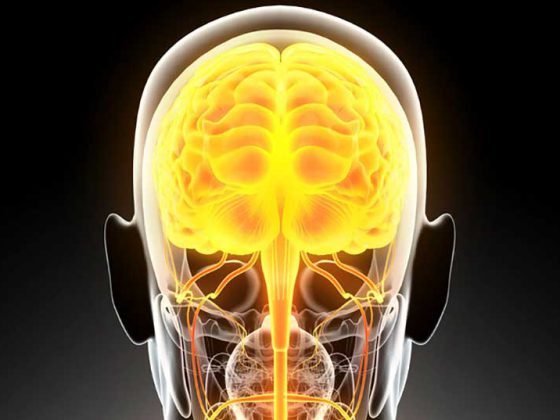

Nach Stroke ist die sofortige Behandlung in spezialisierten Zentren essenziell für ein gutes Therapieergebnis. Frühe Mobilisation fördert – unter Berücksichtigung des neurologisch-medizinischen Zustands des Patienten – dessen funktionelle Unabhängigkeit. Damit die Neurorehabilitation gelingt, muss das interdisziplinäre Team eng zusammenarbeiten.